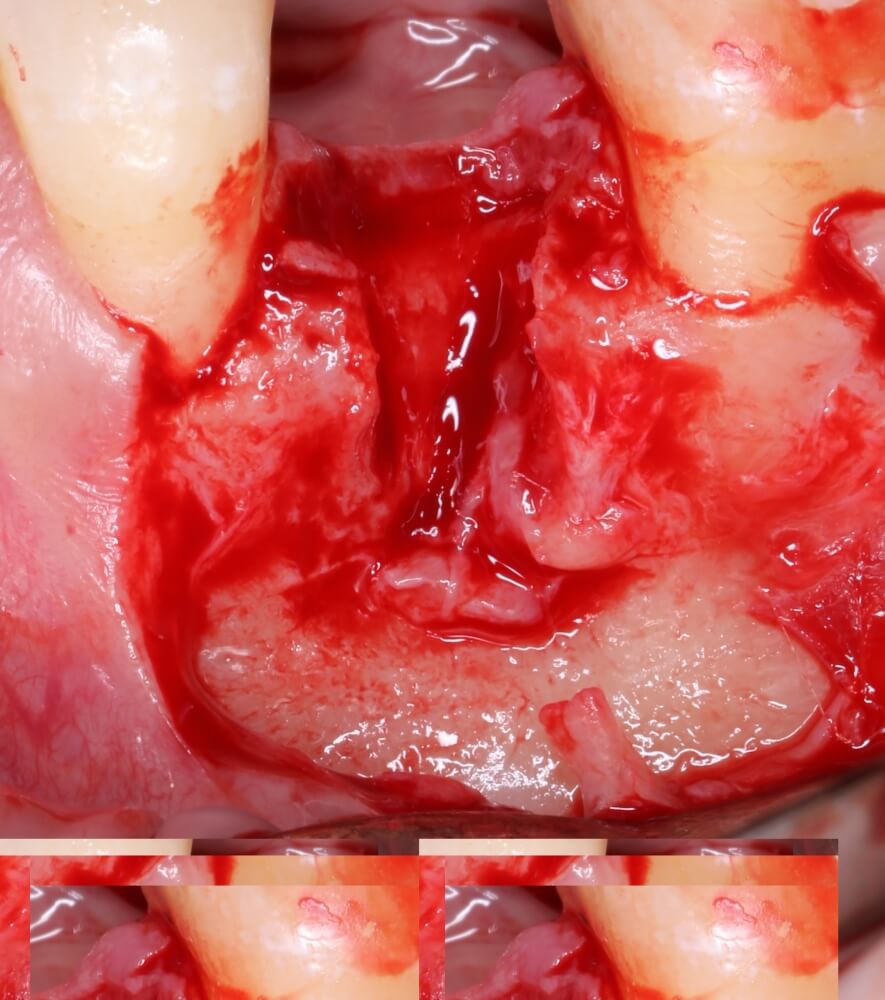

Кстати, обрати внимание на ширину альвеолярного гребня (левая картинка). Она чуть меньше 3 мм. Это объясняет, почему я засомневался в возможности установки имплантатов одновременно с остеопластикой. Понятно и без КЛКТ.

Возвращаемся к основной операционной области. Еще раз посмотрим на альвеолярный гребень, поофигеваем от его ширины и моих грандиозных планов: